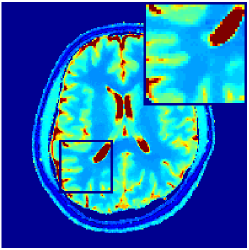

VI-E In-vivo experiments

Two sets of experiments were conducted here: first, we used the 2D and 3D acquisition sequences for scanning a healthy volunteer’s brain (real-world acquisitions). Figures 6 and 7 display the parametric maps reconstructed from 2D spiral and radial readouts. We computed the T1, T2 and proton density (PD) maps using baseline reconstruction algorithms ZF, VS, LR, FLOR, AIR-MRF and our proposed LRTV. While baselines use DM either for quantitative inference or also during reconstruction (i.e. AIR-MRF), we further compare the DM-free LRTV’s performance when cascaded to DM, KM and MRFResnet for quantitative inference. For the 3D spiral acquisitions we compared LRTV and its closest competitor VS in Figure 8. Outcomes from other tested algorithm are displayed in the supplementary materials (Figure S5). Since FLOR does not use dimensionality-reduction, our system ran out of memory during 3D reconstruction; hence results are not reported in this case.

VI-E1 Discussion

The LRTV-DM and LRTV-MRFResnet perform on par, and both outperform all tested baselines for reconstructing T1, T2 and PD maps in all acquisition schemes. This can be observed both visually in Figures 6, 7, 8, S2 and S3, and quantitatively in Table IV across all tested metrics. Other baselines were unable to successfully remove the under-sampling artefacts in TSMIs, and these errors propagated to the parameter inference phase and resulted in inaccurate maps. Temporal-only priors incorporated within LR are shown insufficient to regularise the inverse problem and LR sometimes (e.g. 2D spiral acquisitions) can admit solutions with even stronger artefacts than the model-free ZF baseline. This issue was previously studied for other non-Cartesian MRF readouts that similar to our spiral/radial trajectories, miss to sample the corners of the k-space in all timeframes (see section 2.2.2 and figure 2 in [19]). In the absence of reference for the k-space corners information, the LR iterations despite minimising the objective can converge to solutions with high-frequency artefacts, as visible in the computed maps. This highlights the need for adding an appropriate spatial-domain regularisation. FLOR reduces the LR’s artefacts but this improvement is limited because the suggested nuclear norm penalty does not incorporate an explicit spatial regularisation. Further for reducing artefacts, FLOR can introduce an undesirable bias in the computed T1/T2 maps e.g. see error maps in Figures S2 and S3. The non model-based VS baseline incorporates spatial regularisation and results in spatially smoother maps than ZF and LR, but it is unable to output artefact-free images. Further and consistent with our in-vitro experiment, we observe that VS overestimates the T2 values (e.g. in White and Grey matter regions) in tested 2D acquisitions i.e. the spatial regularisation trades off agains the quantification accuracy. The model-based AIR-MRF adds spatial regularisation through 2D/3D low-pass Gaussian filters however this trades off the sharpness of the computed maps and can increase the errors at the tissue boundaries (we searched Gaussian spreads that keep the blurs and high-frequency artefacts minimal). For our acquisition readouts, Gaussian filters performed better than disk filters of [19] for avoiding strong Gibbs artefacts. On the other hand, the spatiotemporally regularised LRTV greatly improves the TSMI reconstructions i.e. 4 dB enhancement compared to the closest competitor baseline (Table IV). This enables computing accurate and aliased-free multi-parametric inference using DM or the DM-free learning-based alternative MRFResnet as visible in Figures 6, 7, 8, S2 and S3. MRResnet and DM score competitive quantitative inference results i.e. T1 and T2 MAPE less than 5% and 9%, respectively (Table IV). KM also outputs comparably accurate T1 maps, however this shallow learning model despite having a model size larger than MRFResnet, is unable to learn accurate T2/PD quantification and it results in poor estimated maps, consistent with our observations in section VI-C.